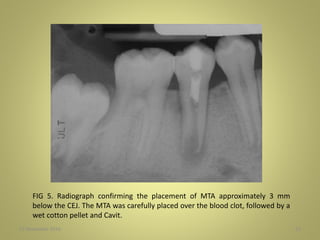

FIG 5. Radiograph confirming the placement of MTA approximately 3 mm

below the CEJ. The MTA was carefully placed over the blood clot, followed by a

wet cotton pellet and Cavit.